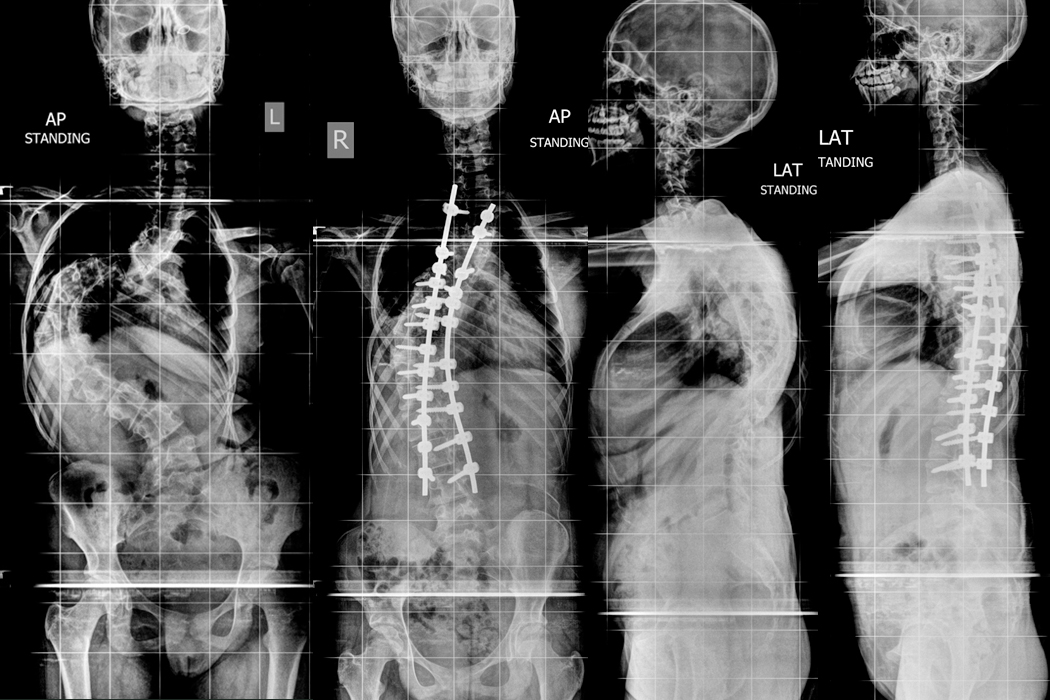

An 8 year old child presented with deformity of back (scoliosis) in 2013. Then he was applied Growing Rod construct and was under regular follow up. In every 6 months distraction of Growing Rods were done for the last 8 years. Finally surgery of Posterior scoliosis correction and fusion was done on 20.08.2021.

Hover over the image to view Pre & Post-op X-Rays